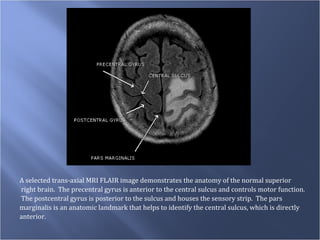

A selected trans-axial MRI FLAIR image demonstrates the anatomy of the normal superior right brain.  The precentral gyrus is anterior to the central sulcus and controls motor function.  The postcentral gyrus is posterior to the sulcus and houses the sensory strip.  The pars  marginalis is an anatomic landmark that helps to identify the central sulcus, which is directly  anterior.

A selected trans-axialMRI FLAIR image demonstrates the anatomy of the normal superior right brain. The precentral gyrus is anterior to the central sulcus and controls motor function. The postcentral gyrus is posterior to the sulcus and houses the sensory strip. The pars marginalis is an anatomic landmark that helps to identify the central sulcus, which is directly anterior.